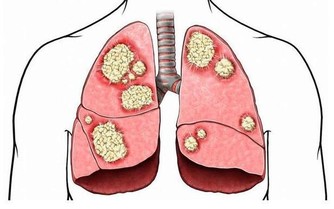

過敏表現常在接觸過敏原半小時至數小時後出現。一般表現如下:煩躁、心慌、胸悶、咽部不適、視物模糊、疲勞、易激惹、緊張、自控力下降、忍耐力下降、情緒失控、皮膚潮紅、紫癜、皮疹、耳道濕潤、鼻塞、鼻涕、鼻塞、噴嚏、眼瞼浮腫、腹痛、腹瀉、多汗、咳嗽,哮喘,呼吸淺快、血壓降低、關節冷痛等等。可見於多種過敏性疾病(如過敏性哮喘、咳嗽、紫癜、皮炎、鼻炎)、一些易激綜合徵(比如腸易激,還有情緒易激等等)、濕疹、痛經、咽炎等等。